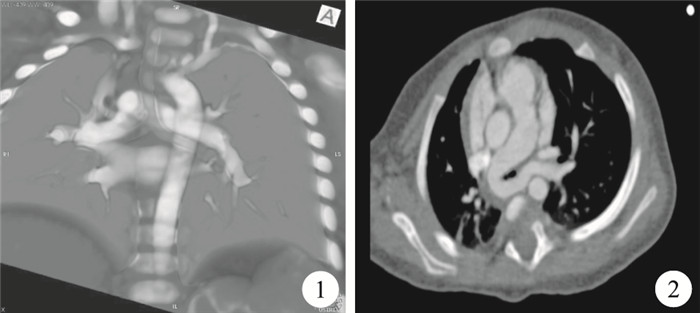

臨床資料??患者,男,6個月。因“反復氣喘2+個月”入院。入院查體可于胸骨左緣第2~3肋間聞及輕微連續性雜音,肺部聽診可聞喘鳴。入院后心臟彩色超聲心動圖提示“先天性心臟病:動脈導管未閉”,但彩色超聲心動圖檢查未能清楚顯示左肺動脈開口。結合患兒臨床表現,行胸部血管增強CT掃描后發現“左肺動脈開口于右肺動脈中段后側壁,包繞氣管走行于其后方,致氣道局部狹窄”,遂補充診斷“肺動脈吊帶”。患兒胸部CT同時意外發現“左肺動脈包繞氣管”處見“氣管壁局部呈指狀突出形成約3 mm×4 mm憩室” (圖 1、圖 2)。術中充分游離主肺動脈、右肺動脈及開口于右肺動脈后壁的左肺動脈。可觸及左肺動脈包繞處突起憩室。自左肺動脈開口離斷左肺動脈,將其重新置于氣管前方,于主肺動脈左側壁行端-側吻合完成重建。結扎動脈導管。因患兒并無反復氣道感染表現,故未處理氣管憩室。患兒術后恢復順利,隨訪6個月無明顯癥狀。

討論??氣管憩室是少見的氣管良性疾病,多為意外發現,一般分為先天性和獲得性兩種,二者的起源部位、特征、組織學結構等都有所不同,后者更為常見[1]。先天性憩室類似于氣管發育過程中突出的“分支”,具有氣管各層的解剖結構。而獲得性憩室多為因氣道內壓力改變而產生的黏膜疝出,其腔壁主要由氣管上皮構成,而不包含平滑肌和軟骨。氣管憩室多無臨床癥狀,但也偶見反復氣道感染及慢性咳嗽患者[2]。肺動脈吊帶為少見先天性心臟病,目前認為多由胚胎時期肺血管起源異常所致,其主要臨床意義為異常起源的左肺動脈包繞氣管形成局部壓迫和相應的臨床癥狀。以上兩種少見疾病的組合非常罕見,僅在2009年由韓國醫生Jae Sung Son及其同事報道1例[3],且該例氣管憩室發生于左肺動脈包繞部位的上方,兩者并無明顯相關性,似為巧合。本例氣管憩室恰發生于左肺動脈包繞壓迫處,氣管憩室的形成可能與局部黏膜受壓變形及局部氣道狹窄所致氣壓升高有直接的關系。提示諸如肺動脈吊帶等可能對氣管局部造成壓迫的先天性血管畸形與氣管憩室的發生之間可能存在聯系,應引起臨床重視。